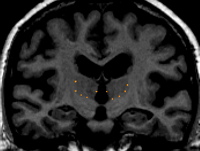

By drawing many sulci lines in the dorsal axial view, the mid axial view and the ventral axial view of the thalamus you can obtain a skeleton of the outline of the thalamus produced by "dots" marking the sagittally drawn sulci in the coronal view. This gives you a guide to find the best fit contour line.

The hypothalamic fissure serves as the inferior border of the thalamus and a dividing line between the thalamus and the ventral diencephalon (VDC). This border is marked by drawing sulci in the medial sagittal views of the thalamus and VDC. The hypothalamic fissure is seen most easily toward the midline in the sagittal view, therefore begin drawing the sulci lines on or close to the most medial sagittal slice. The fissure should be drawn as a line which cups the bottom of the thalamus beginning caudally and moving rostrally as far as possible. It is often advantageous to draw many sulci on consecutive sagittal slices, moving from medial to lateral, in order to see the full extent and curve of the fissure more accurately in the coronal view.

The inferior border of the thalamus can be drawn by connecting the "dots" that result from the sagittally drawn sulci lines in the coronal view.